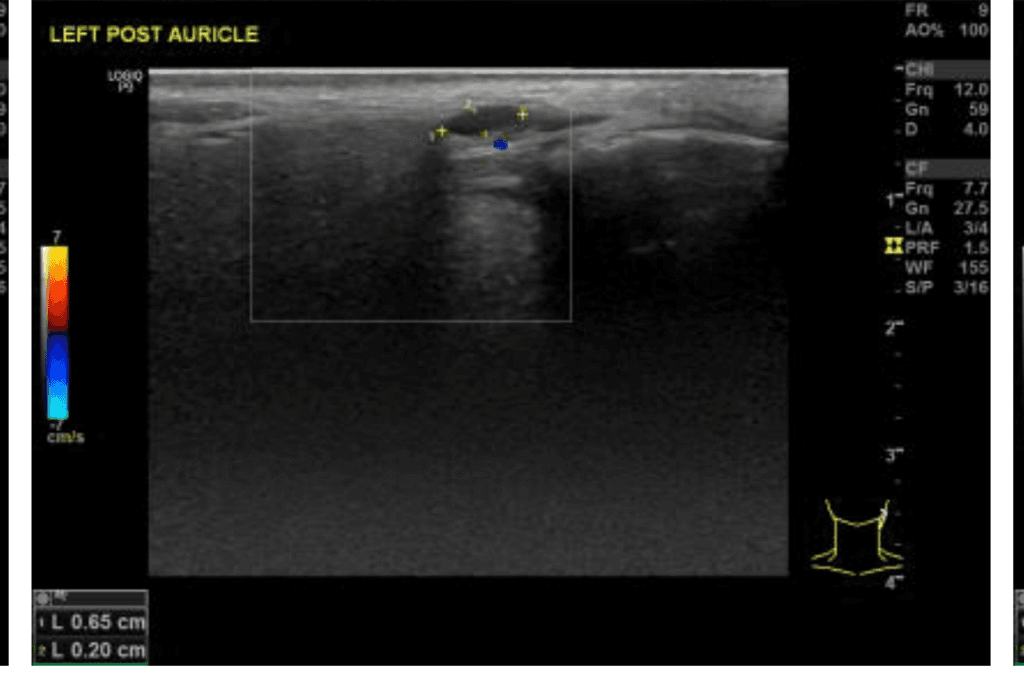

임파선의 경우 보통 0.5cm 전후의 직경을 가지고 있으며, 0.65cm이라면 경도의 붓기가 있는 것으로 생각됩니다. 다만, 일반적으로 1개월 이내에는 호전되는 경우가 많기 때문에 2개월이상 호전되지 않는다면 근처 이비인후과에서 재진료를 보시는 것이 좋을 것으로 보입니다.

귀 밑에 만져지는 딱딱한 혹이 임파선 비대로 진단받은 경우, 해당 임파선은 보통 감염, 염증, 혹은 다른 원인에 의한 면역 반응의 일부로 비대해진 것일 수 있습니다. 0.65cm 크기의 임파선은 많은 경우에 정상 범위 내로 간주되지만, 임파선의 크기가 오랜 기간 동안 변하지 않고 유지된다면, 이는 일반적으로 진정되지 않는 면역 활동을 나타낼 수 있습니다. 대부분의 경우 해로운 상태는 아닙니다. 체중 감소, 발열, 야간 발한 등의 일반적인 감염 증상이나 림프계 이상을 나타내는 다른 증상이 동반되는 경우, 더 심도 있는 검사가 필요할 수 있습니다. 정확한 평가를 위해서는 시간이 지남에 따라 임파선의 변화를 지속적으로 추적하는 것이 중요합니다.